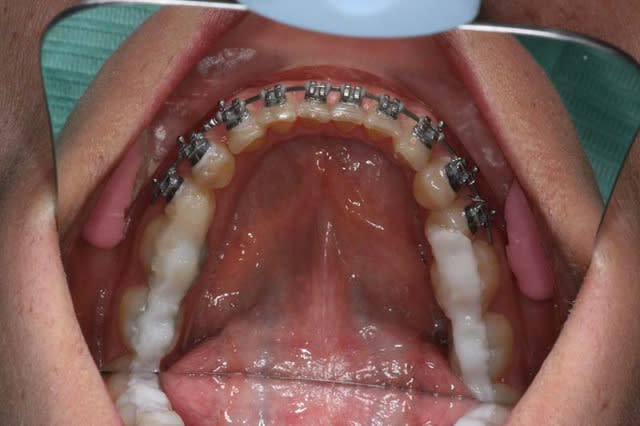

je la traite par les techniques de friction faible, et voici le résultat 1 an après

je ne suis pas en inversé d’articulé Ant. comme je pensais me retrouver !!!

et son profil s’est bien modifié

Tu as placé du compo sur le post du bas, ouvrant la DV post, ce qui change le profil, non ?

"""Tu as placé du compo sur le post du bas, ouvrant la DV post, ce qui change le profil, non ?"""

oui, en cours de TTT.

la derniere Rx. et les photos de visage sont prises avant qu'elle retourne voir son 2° chirurgien et sont sans compo